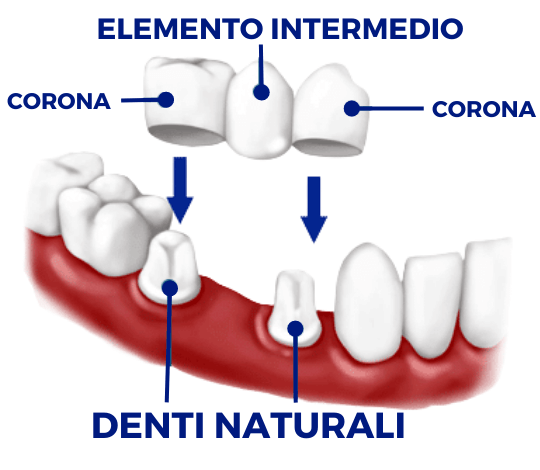

Oltre al ripristino estetico della dentatura, il ponte dentale previene le complicazioni che possono derivare dalla mancanza di un dente. Una volta applicato, completerà il normale processo di masticazione e migliorerà la funzione fonetica.